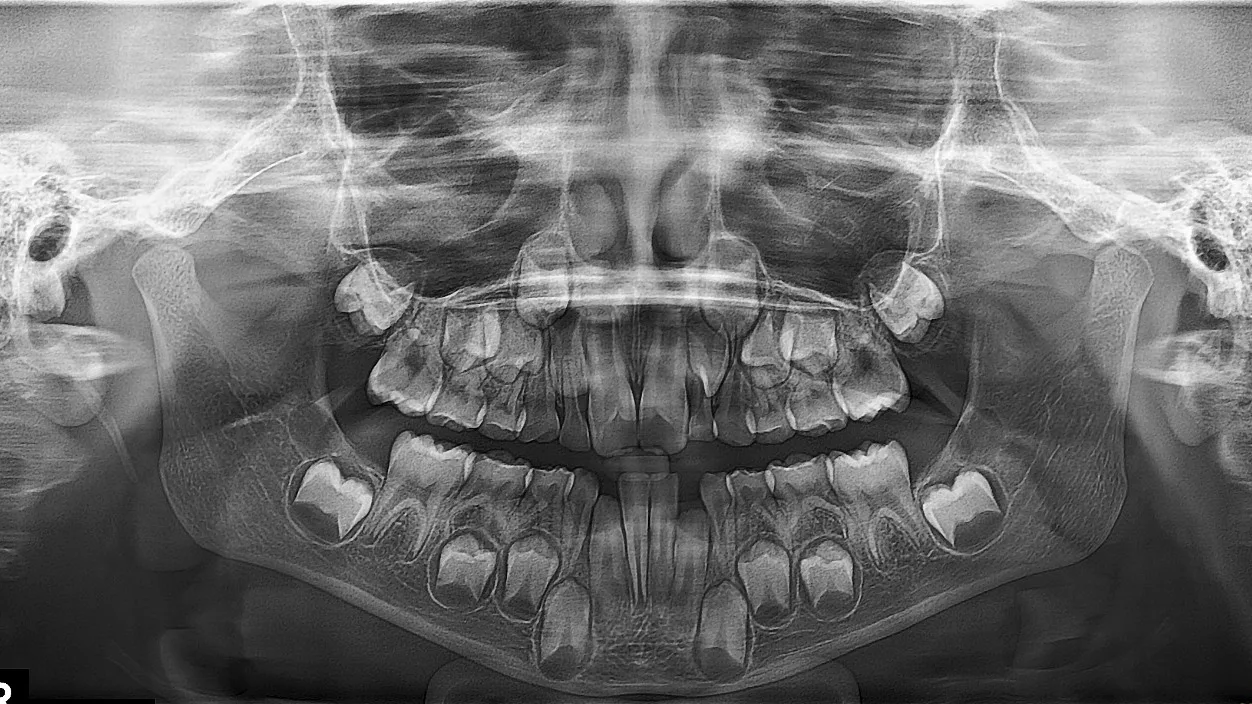

Фотографии и схемы для ОПТГ и мезиального прикуса